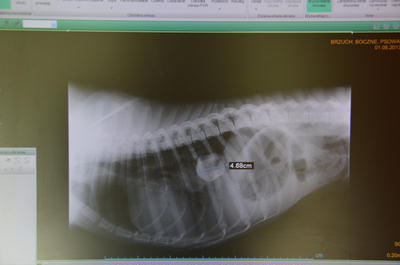

Skręt żołądka.